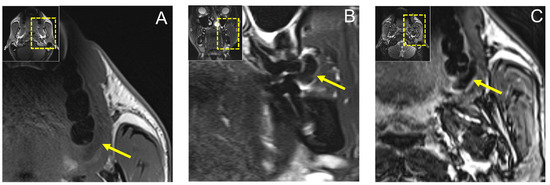

Dental MRI showed a well-demarcated lesion with a maximum extension of 21.3 × 5.6 mm (axial), 13 × 8.6 mm (coronal), and 10.1 × 9.8 mm (sagittal) on a T2 STIR protocol, with homogenous low signal intensity in the central area of the lesion, while the peripheral area showed a high signal intensity. The lesion originated from the planum buccale and did not infiltrate adjacent structures, with a displacement of the second upper molar (Figure 4). The DESS protocol revealed the same hypointense lesion with lower resolution and image quality compared with the STIR protocol (Figure 5). Thus, the radiological findings excluded any further involvement in the head and neck area, the presence of a lipoma, or other space-occupying pathologies, and provided the precise localization and extension of the suspected fibromatous lesion.

Figure 5.

Preoperative MRI of the same lesion using 3D double-echo steady-state (3D-DESS) imaging protocol. (A) Axial, (B) coronal, and (C) sagittal reconstructions visualizing a well-demarcated lesion with a maximum extension of 21.3 × 5.6 mm (axial), 13 × 8.6 mm (coronal), and 10.1 × 9.8 mm (sagittal). For orientation, the dotted rectangles in the corner show the enlarged area. The MR image reconstructions seem to have a slightly lower resolution due to the larger scale along the slice direction.